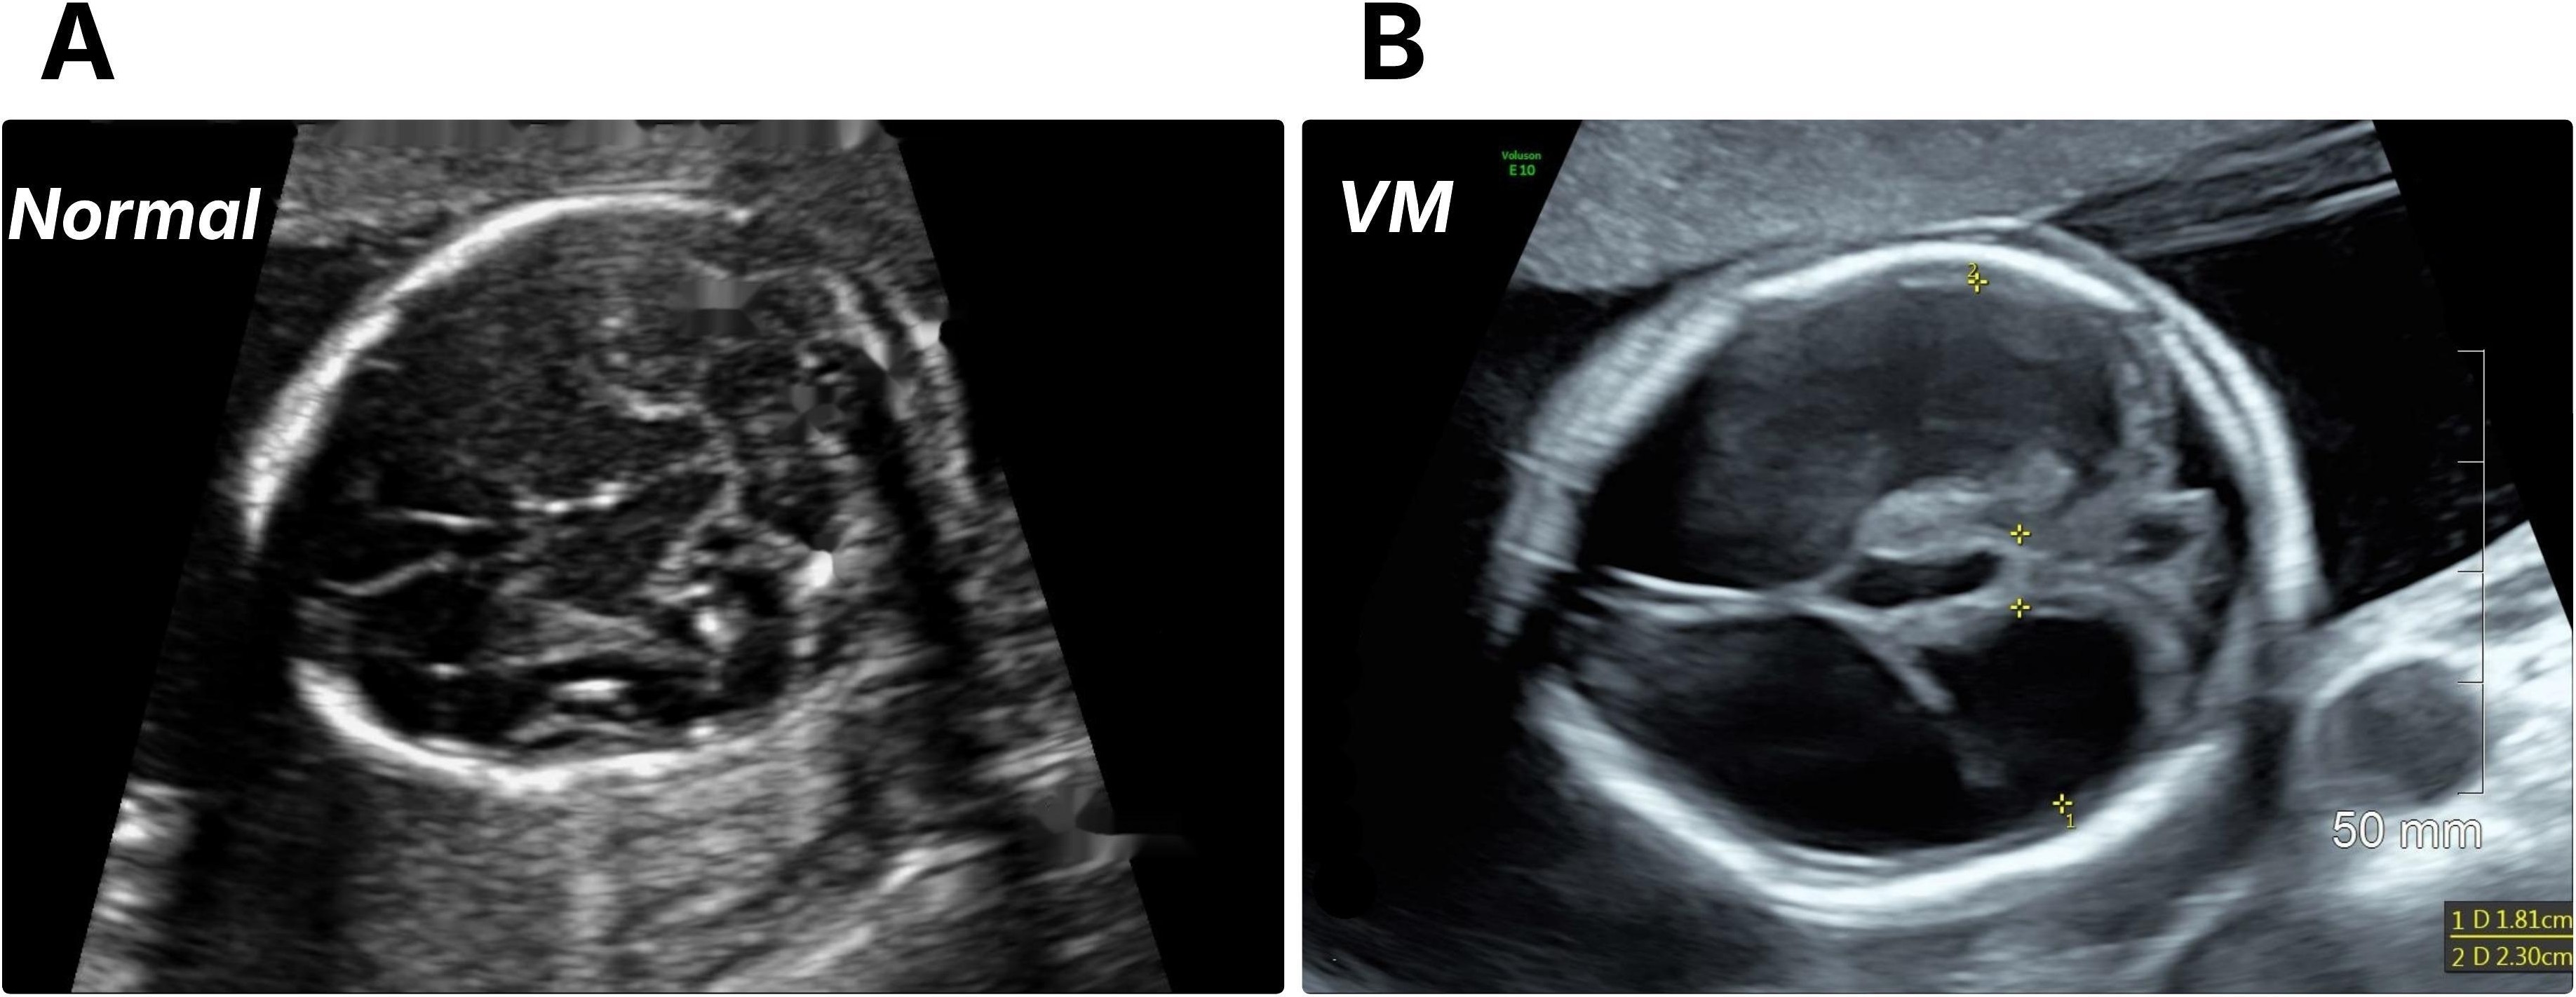

Refer to caption

Figure 1: Prenatal ultrasound comparison of normal and ventriculomegaly (VM) fetal brains. (A) Normal fetal brain showing typical lateral ventricle size and configuration. (B) Fetal brain with VM demonstrating enlarged lateral ventricles.

The study was approved by the Ottawa Health Science Network Research Ethics Board (OHSN-REB). This retrospective study included ultrasound images from pregnant individuals with singleton or twin pregnancies obtained between June 2014 and May 2021 at a tertiary hospital in Eastern Ontario, Canada. All images were acquired using either a GE Voluson TM V830 or V730 ultrasound system by professional obstetric sonographers and interpreted by maternal-fetal medicine specialists. Among these, we selected fetal brain images with or without VM that were obtained between 18 and 24 weeks of gestation (Fig. 1 shows an example of each class). Multiple images were collected from patients who underwent several US examinations within the designated gestational age (GA) range.